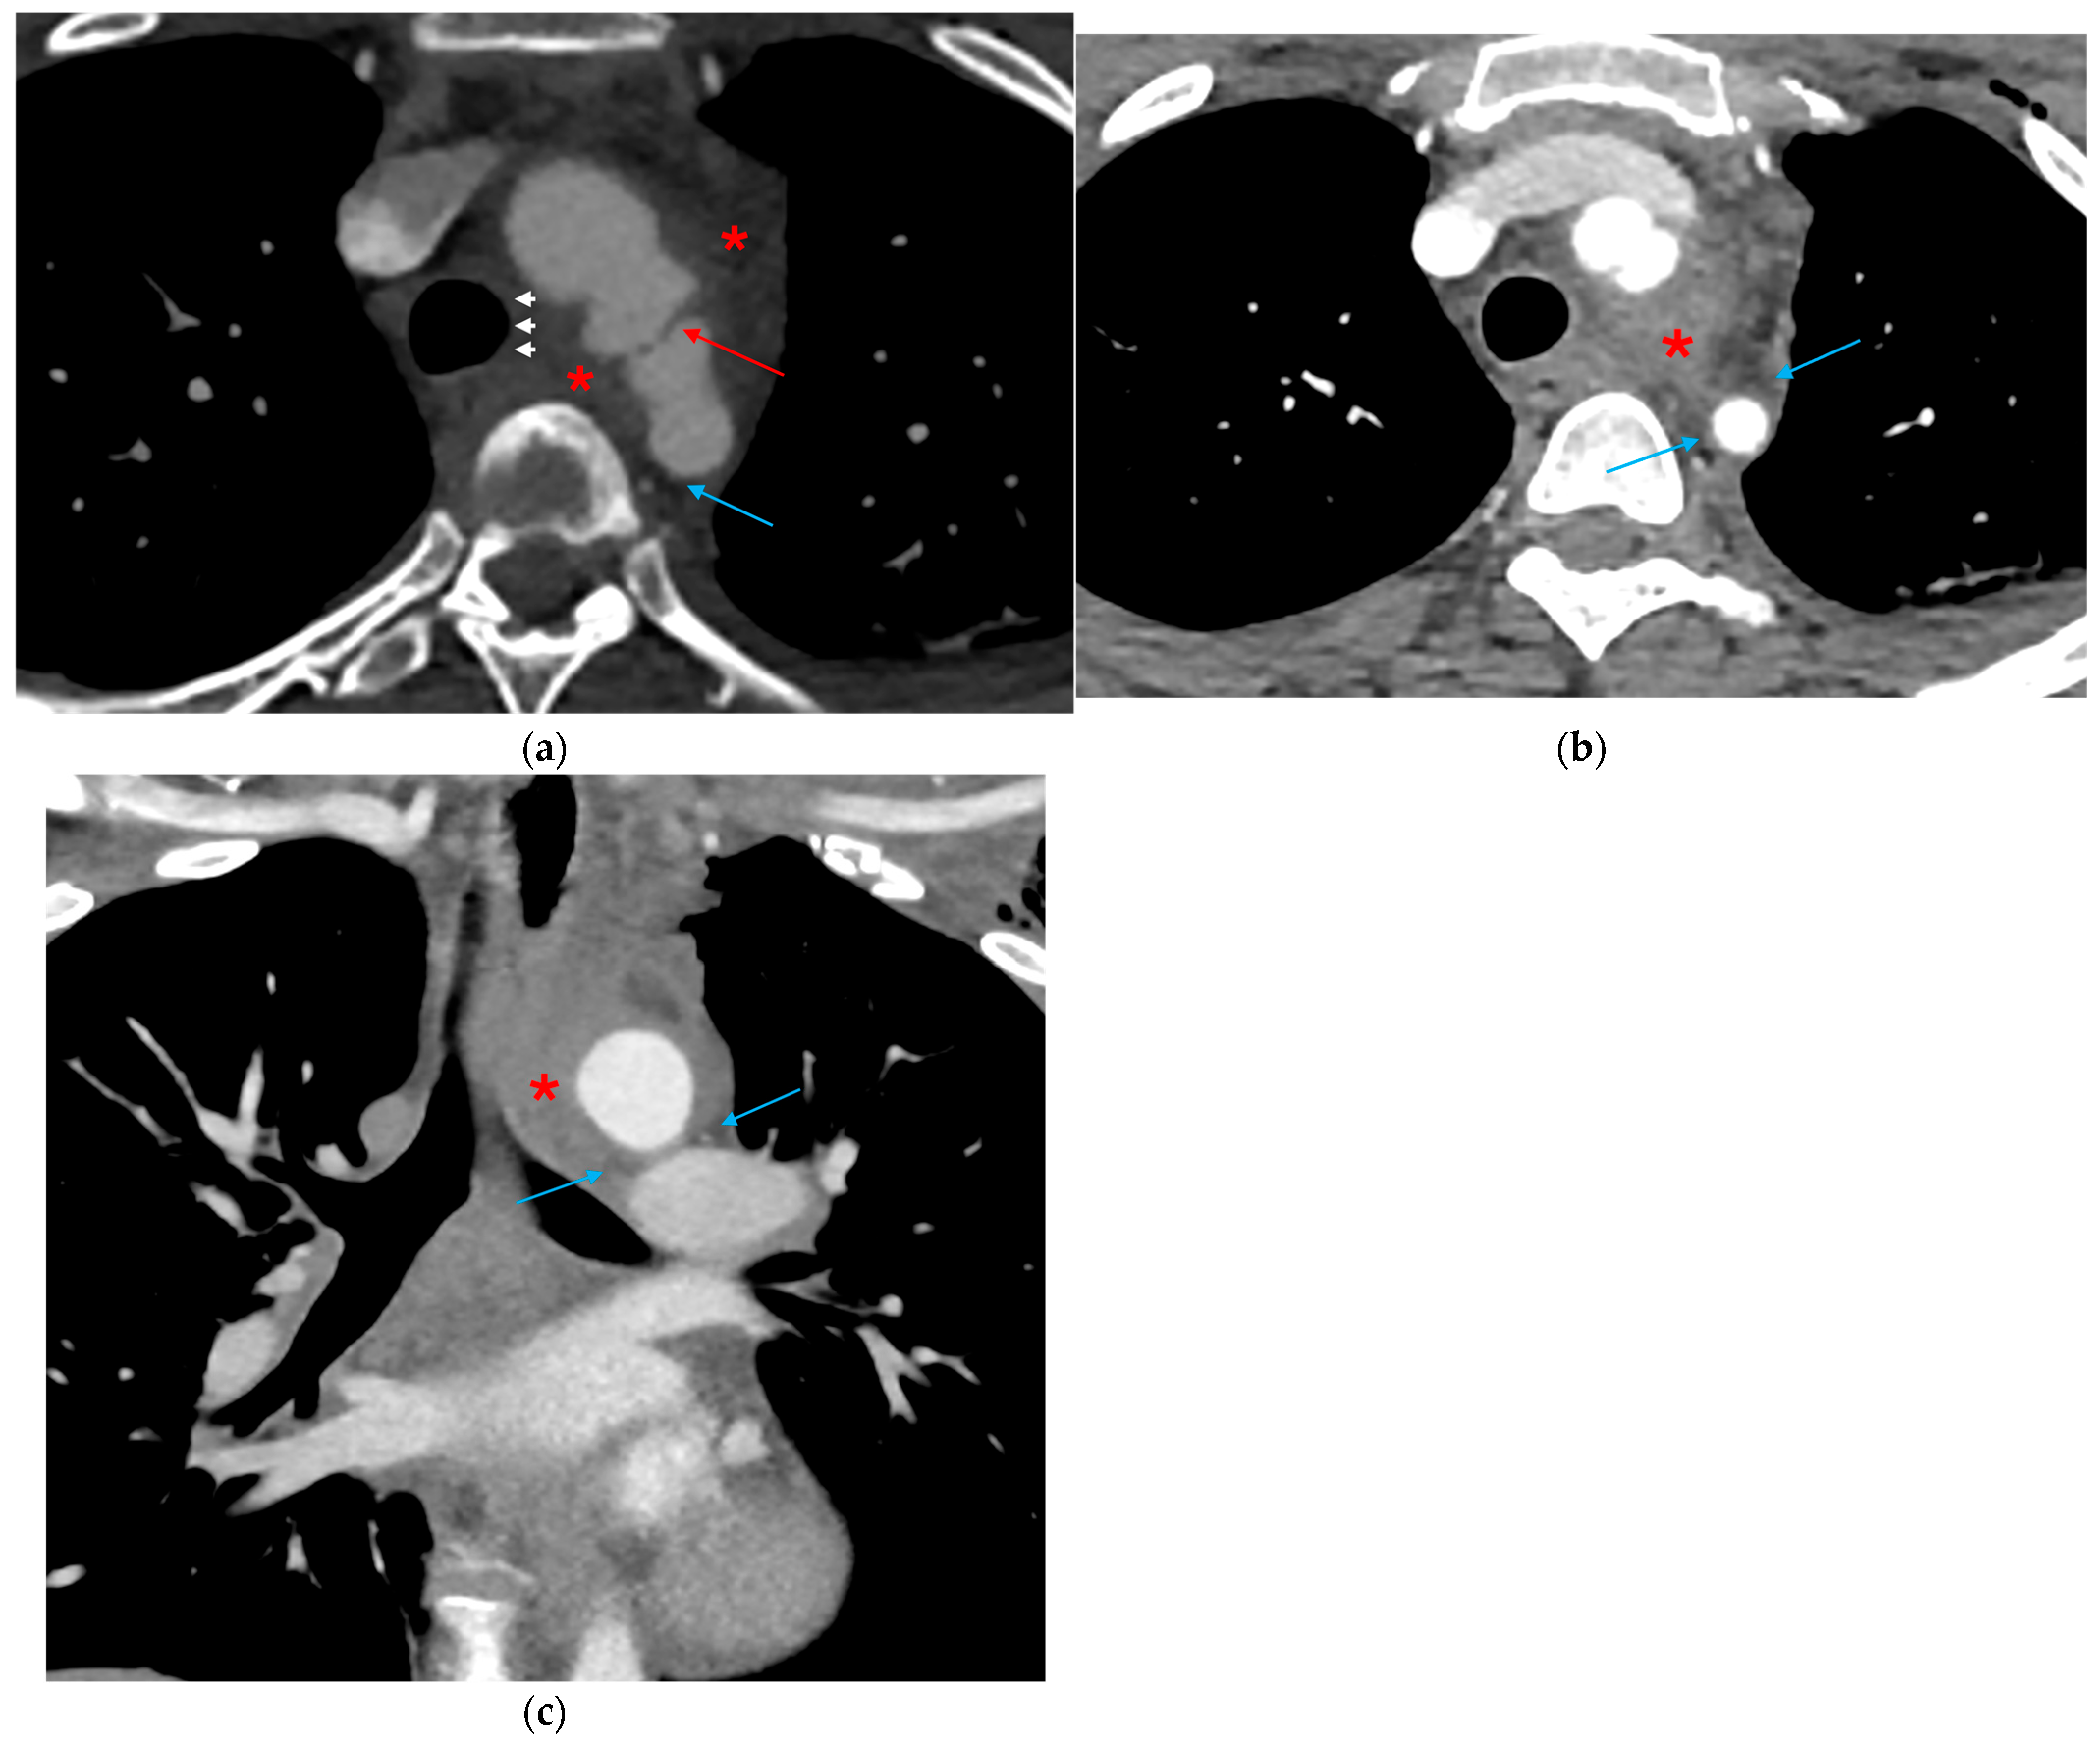

3.1.1. Direct Signs of Aortic Injury

3.1.2. Indirect Signs of Aortic Injury